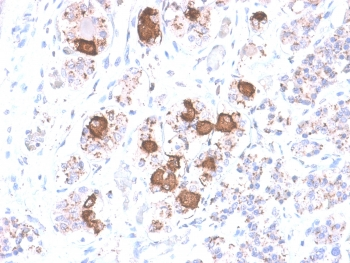

IHC testing of FFPE human pituitary gland with ACTH antibody (clone CLIP/1407). Required HIER: steam sections in 10mM citrate buffer, pH6, for 10-20 min.

IHC testing of FFPE human pituitary gland with ACTH antibody (clone CLIP/1407). Required HIER: steam sections in EDTA buffer, pH9, for 10-20 min.

IHC testing of FFPE human pituitary adenoma with ACTH antibody (clone CLIP/1407). Required HIER: steam sections in EDTA buffer, pH9, for 10-20 min.